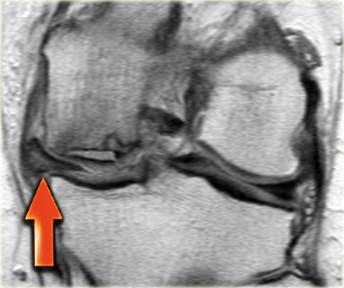

Cùng ca bệnh trên với hình ảnh mặt phẳng sagittal.

Lưu ý phần bị rách của sụn chêm chạy ra phía trước qua hố gian lồi cầu (các mũi tên)

- Thông thường chỉ có hai cấu trúc chạy trong hố gian lồi cầu. Ở đây chúng ta thấy dây chằng chéo sau bình thường.

- Dây chằng chéo trước bình thường.

- Phần bị rách của sừng sau như là ‘cấu trúc thứ ba’

trong hố gian lồi cầu. - Phần bị rách chạy ra phía trước.

- Phần bị rách nhập vào sừng trước và giả tạo hình ảnh rách dọc ở sừng trước.

Lưu ý phần còn lại nhỏ của sừng sau.